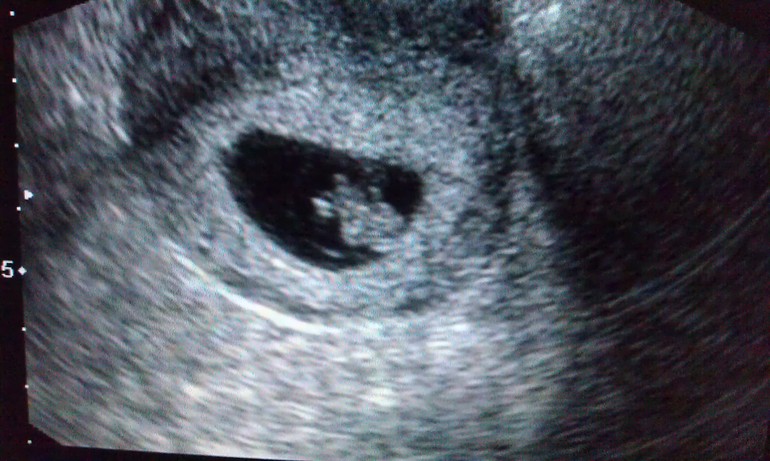

УЗИ, КТГ, доплерИ так, в 7 н. и 6 дн. наконец то мы попали на наше первое УЗИ. Конечно немного переживала как там обстоят дела, но результат меня очень обрадовал. Развиваемся мы нормально, посмотрела сердечко, оно так бьётся, прям выпрыгивает. Послушать не получилось, наверно аппарат не позволял, но увиденного вполне хватило.

На память добавляю фотки результата УЗИ и фотку нашего пузожителя.